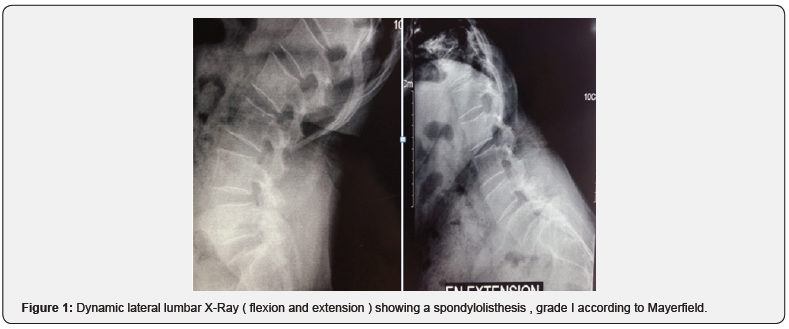

25 patients, 88% of whom were women, were included in our work, the average age was 54 years (34 to 70 years). At the time of the initial examination, all the patients had a severe mechanical low back pain which was rebellious to a well-managed medical treatment, 80% of the patients complained of radiculalgia, most often affecting the L5 and / or S1 territory. 14 patients had neurological claudications, 4 patients with motor neurological deficit; These disorders are in the form of functional impairment affecting the two lower limbs with an average rating of 3/5, 14 patients with sensory disorders : Hypoesthesia and Tingling of the lower limbs, and genito-sphincter disorders in two patients. The preoperative evaluation was based on the assessment of low back and radicular pain according to the visual analogue scale evaluation (VAS), the average score was 6 (4-9), and the patients’ quality of life evaluated according to the score d ‘Oswerstry (satisfaction index) with an average of 62 (40-80). The preoperative radiological analysis in our patients was based on x-rays of the lumbar spine (antero-posterior and lateral views) , dynamic images in flexion and extension (Figure 1), as well as magnetic resonance imaging. Isthmic lysis was the most frequent etiology of spondylolisthesis (56%), L5-S1 was its most frequent site (15 cases), the degree of slippage evaluated according to the MEYERDING classification showed that 56% of patients had a Grade I (Figure 1), and 44% had a Grade II. On MRI, stage I disc disease according to the MODIC classification was differentiated in 12 patients, stage II in 8 patients (Figure 2), 16 patients had an associated herniated disc, i.e. 64%, among the 25 cases, 14 patients had root compression i.e 56%.